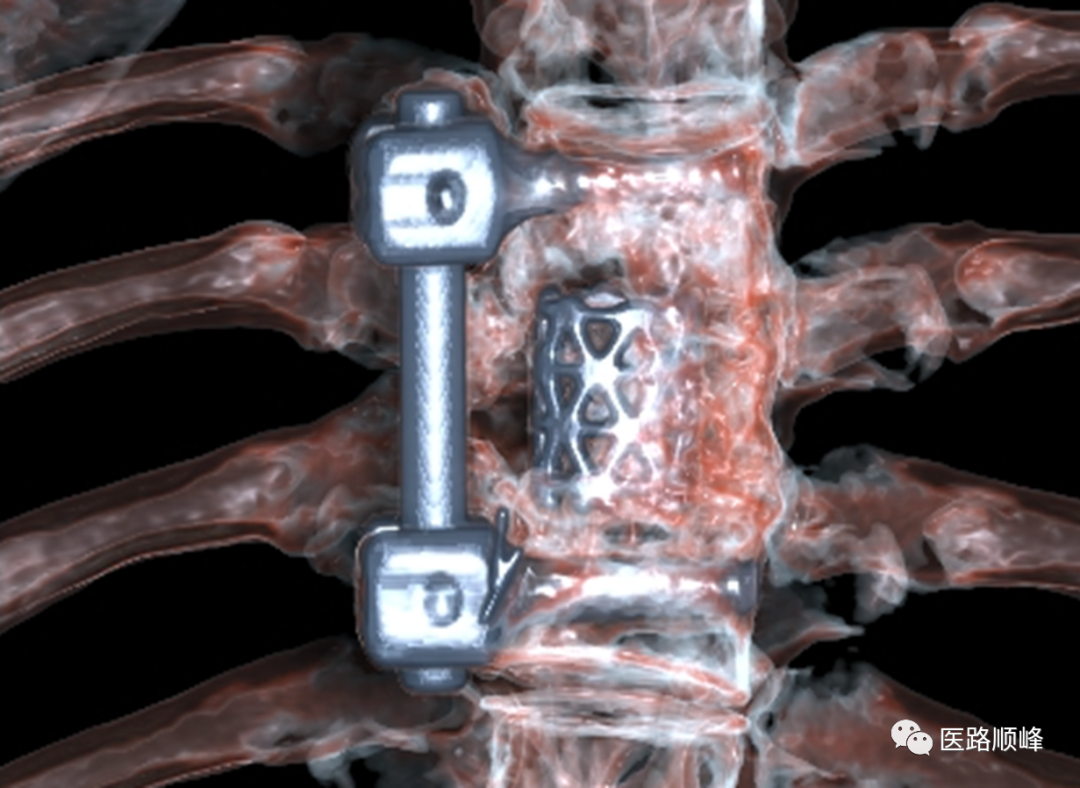

• O-MAR去金属伪影

ct为什么需要预热机器Computed Tomography专栏:Incisive CT 球管预热_https://www.jmylbn.com_新闻资讯_第21张